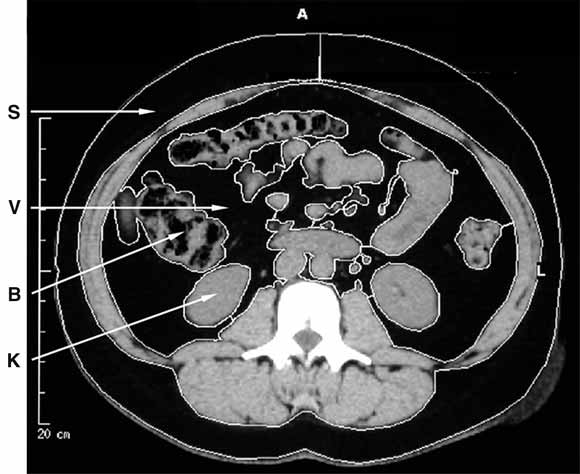

5: Central obesity in polycystic ovary syndrome

Computed tomography of the abdomen in polycystic ovary syndrome, showing subcutaneous (S) and visceral (V) fat, surrounding bowel (B) and kidneys (K).